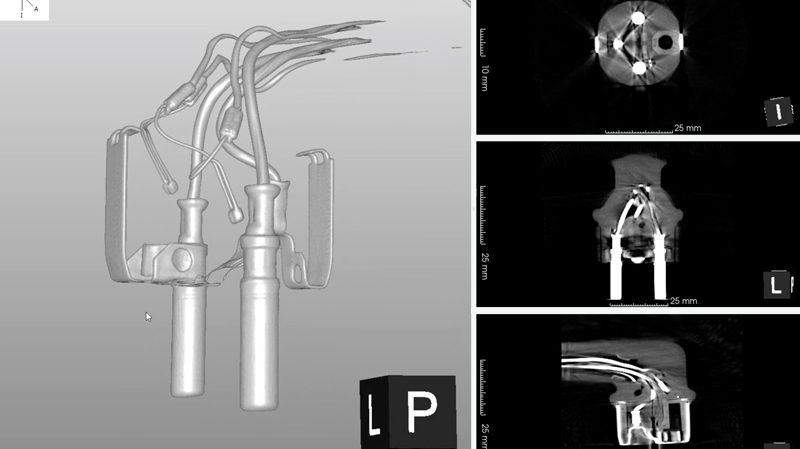

NAOMi-CTで色々なものをブツ切りにしてみました。※クリックすると拡大画像をご覧いただけます。